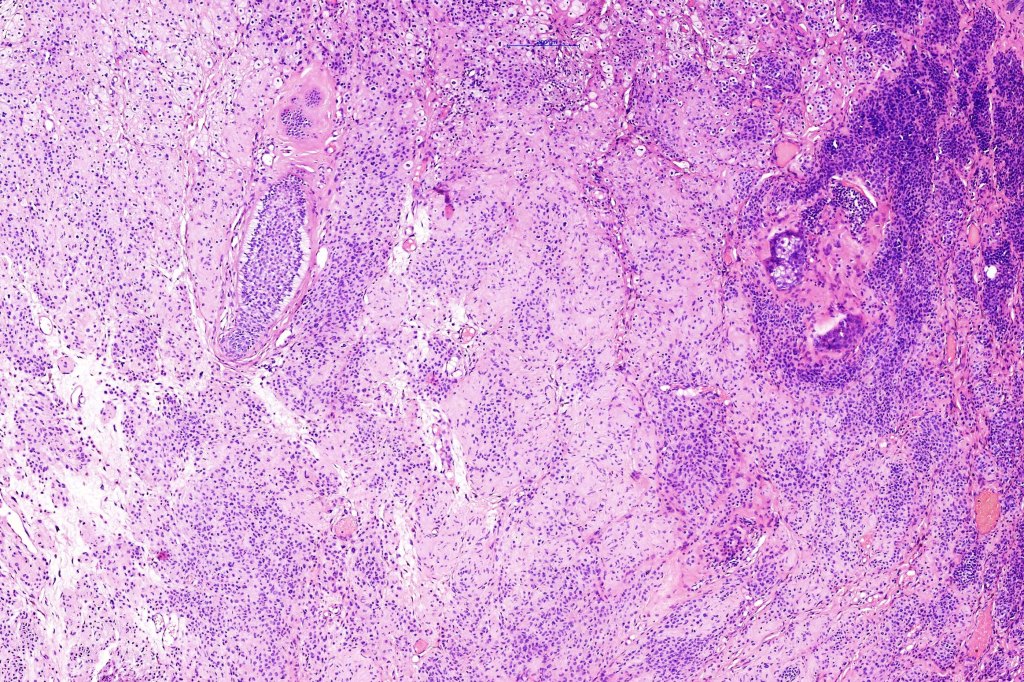

Histological features

.Balloon cell change is most often seen in banal melanocytic nevi but it has also rarely been described in cellular blue nevus, dysplastic nevus, combined nevus, halo nevus & Spitz nevus. Lesions with <50% of balloon cells are sometimes described as nevi with balloon cells. Nevi with >50% balloon cells are described as balloon cell nevus.

.Balloon cell nevs genrally has uniform, hyperchromatic nuceli (as opposed to the vesicular nuclei with prominent nucleoli) seen in melanoma. Mitoses are absent.(In my experience, balloon cell melanoma is more common than balloon cell nevus).

The importance of the entity is that it must always be distinguished from balloon cell melanoma. All cases should be scrutinized very carefully for pleomorphism and mitotic activiy before rendering a diagnosis of balloon cell nevus.